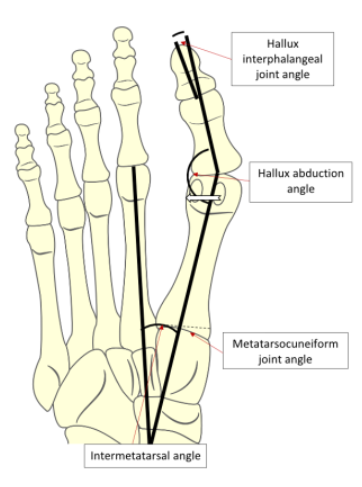

방사선 촬영(X-ray)을 통해 엄지발가락과 중족골의 각도, 관절 변형, 퇴행성 변화 등을 평가함

정상인의 무지외반각은 15도 이하, 20~40도는 중등도, 40도 이상은 중증으로 구분